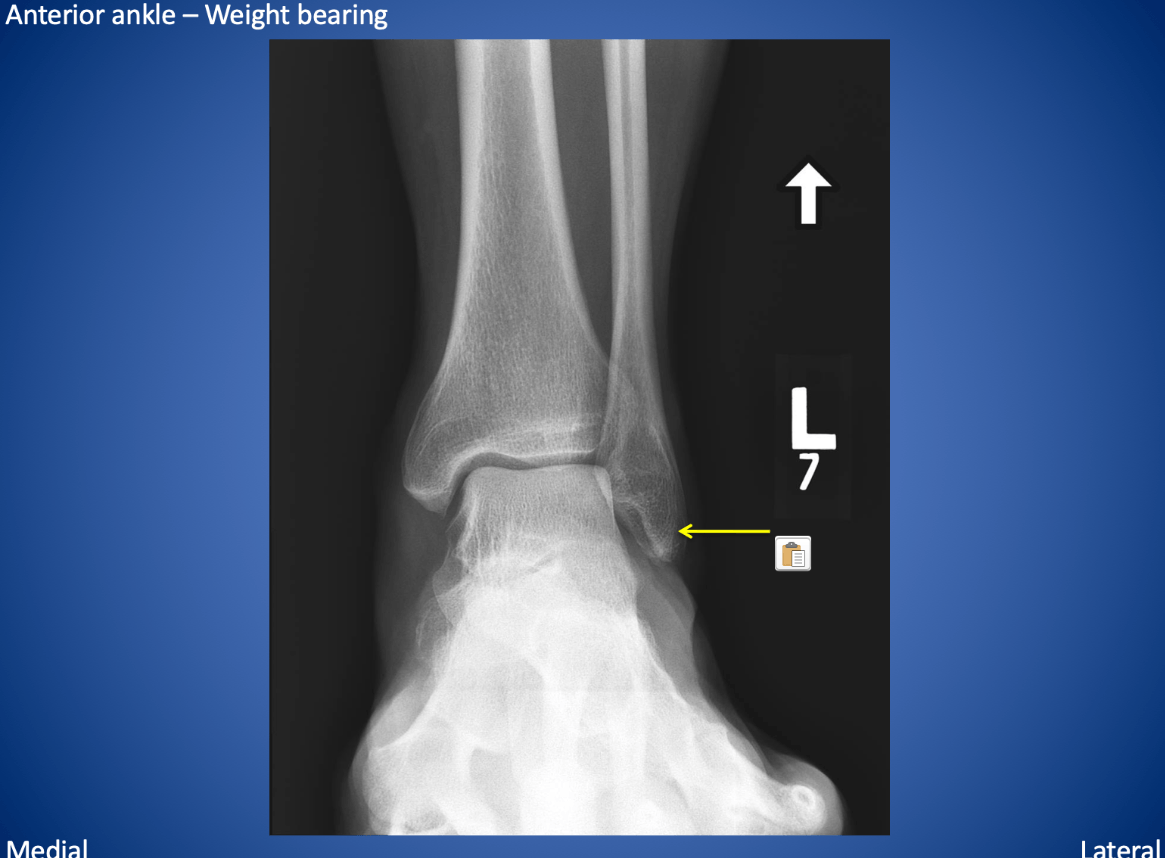

The yellow arrow is pointing to this structure.

What is the lateral malleolus?